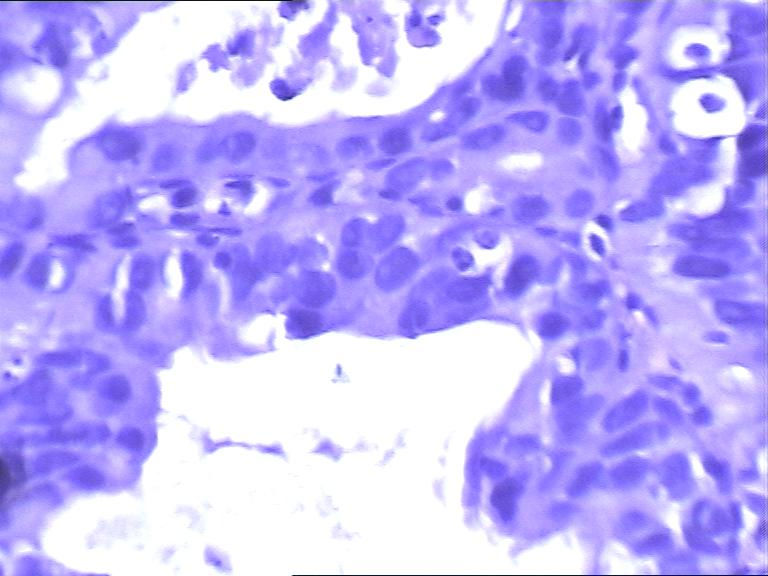

男 63岁 胃镜提示残胃炎

胃镜活检图1

胃镜活检图2

高级别瘤变

高级别上皮内瘤变。他原先是因为什么病做的手术?

低级别病变

bugougaojibie不够高级别,是不是一种炎症反应

2010年2月以低分化腺癌行近段胃癌根治术,术后给予奥沙利铂、5-氟尿嘧啶化、cf等化疗4次。

高级别上皮内瘤变

高级别上皮内瘤变,不知胃镜下病变范围

结构的紊乱考虑手术所致,细胞的异性可能为炎性所致,